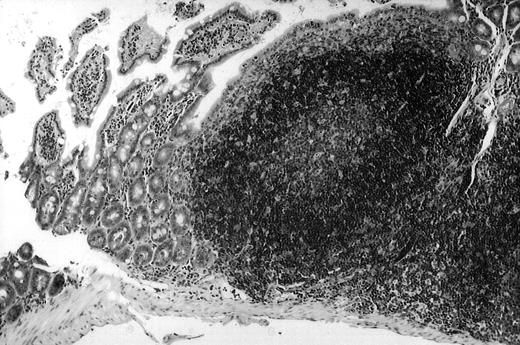

To analyze expression of the human CD40L protein in murine tissues, samples from the small intestine, colon, liver, and spleen were analyzed by HE staining as well as immunohistochemistry. We found that in mice immunized with ST40L, the Peyer's patches were prominent (Figure 1A), and the majority of cells in the Peyer's patches could be seen to express the human CD40L protein (positive: brown or yellow color; negative: blue color) (Figure 1B). There were a few CD40L+ cells in spleen, but not in liver. In contrast, human CD40L was not detectable in the Peyer's patches of mice treated with ST (Figure 1C). To further confirm the secretion of human soluble CD40L by transfected murine cells into the sera, we next examined it by ELISA (Figure 2). Human soluble CD40L protein was detectable only in BALB/c mice treated with ST40L with or without administration of BCL cells, but not detectable in mice treated with ST and/or BCL cells. The level of soluble CD40L protein in the sera peaked at 1 week after oral administration and was detectable until 7 to 8 weeks.

Presence of transduced human CD40L protein in mice treated with ST40L.

(A) HE staining of intestine ( × 100) of BALB/c mice killed 1 week after oral administration of ST40L. (B) Immunostaining of Peyer's patches using antihuman CD40L Ab (×400) of BALB/c mice killed 1 week after oral administration of ST40L. (C) Immunostaining of Peyer's patches using antihuman CD40L Ab (×400) of BALB/c mice killed 1 week after oral administration of ST.